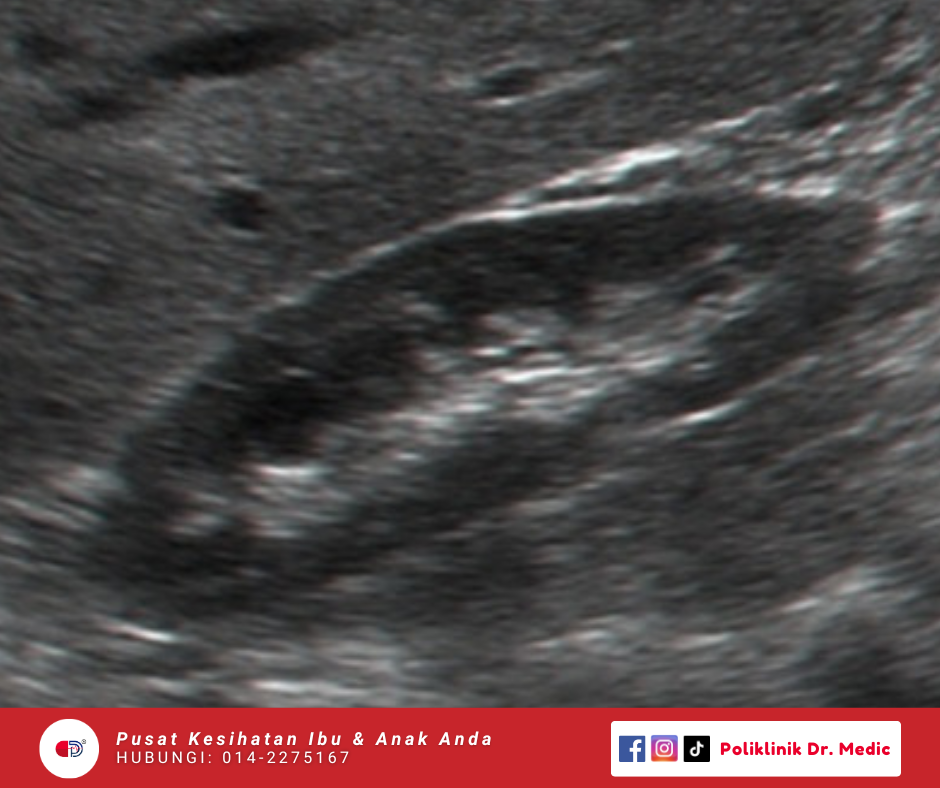

Transvaginal Scan

Imbasan dalaman guna probe kecil melalui faraj untuk lihat rahim, ovari, dan kawasan sekeliling dengan lebih jelas. Biasanya dibuat untuk kes macam period tak teratur, cyst, pendarahan luar biasa, atau masalah kesuburan.

RM60